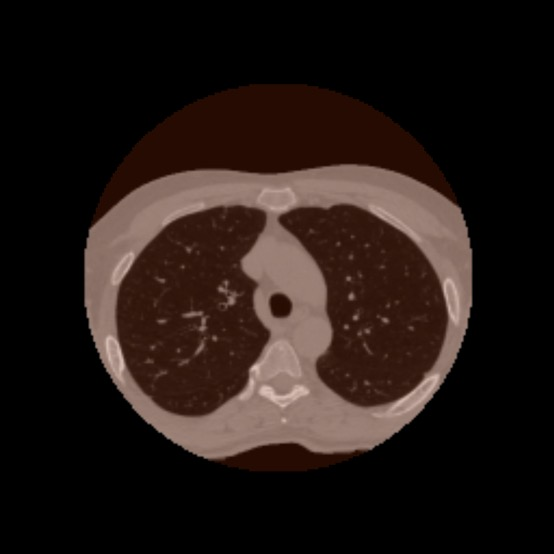

Anatomically consistent field-of-view (FOV) completion to recover truncated body sections has important applications in quantitative analyses of computed tomography (CT) with limited FOV. Existing solution based on conditional generative models relies on the fidelity of synthetic truncation patterns at training phase, which poses limitations for the generalizability of the method to potential unknown types of truncation. In this study, we evaluate a zero-shot method based on a pretrained unconditional generative diffusion prior, where truncation pattern with arbitrary forms can be specified at inference phase. In evaluation on simulated chest CT slices with synthetic FOV truncation, the method is capable of recovering anatomically consistent body sections and subcutaneous adipose tissue measurement error caused by FOV truncation. However, the correction accuracy is inferior to the conditionally trained counterpart.

翻译:按比例一致的FOV完成可以恢复被截断的身体部位,对于受限FOV的计算机断层扫描(CT)进行定量分析具有重要应用。 现有的基于条件生成模型的解决方案依赖于训练阶段合成截断模式的保真度,这为该方法的泛化能力到未知类型的截断带来了限制。 在这项研究中,我们评估了一种基于预训练的无条件生成扩散优先的零样本方法,在推理阶段可以指定任意形式的截断模式。 通过在模拟胸部CT切片上进行评估,该方法能够恢复按比例一致的身体部位和由FOV截断引起的皮下脂肪组织测量误差。 然而,纠正精度不如有条件的训练对照组。